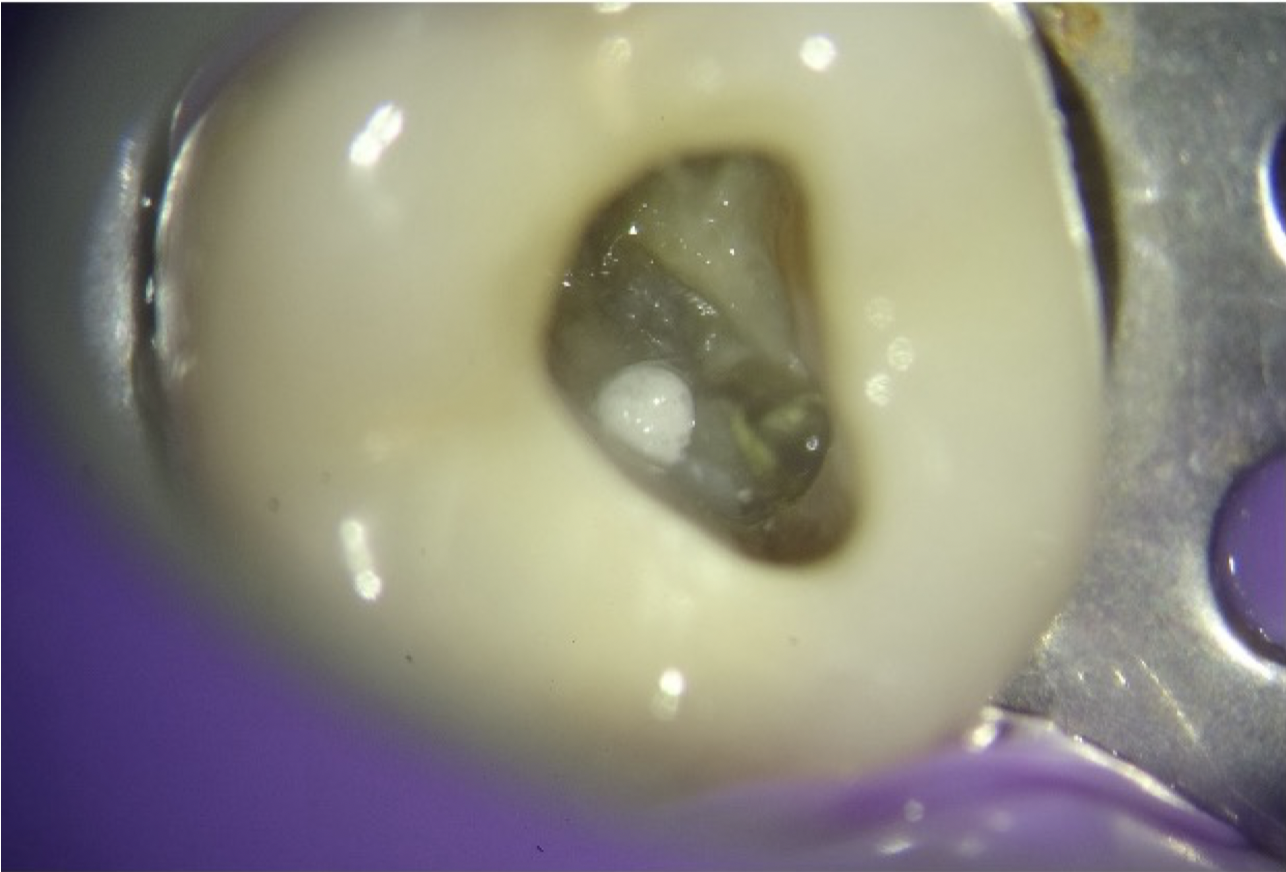

Fig. 3

After administration of local anaesthesia in tooth 36, strict rubber dam isolation was achieved to ensure an aseptic operating field (Fig. 3). The existing access cavity was carefully refined to improve visualisation of the pulpal floor. All procedures were performed under a dental operating microscope, allowing enhanced precision and minimising the risk of further procedural damage. The pulp chamber was gently debrided, and the perforation site was clearly visualised in the furcation region, exhibiting active bleeding consistent with communication with the periodontal tissues.

The initial phase of management focused on haemostasis and decontamination of the defect (Fig. 4). Controlled irrigation was performed using 3% sodium hypochlorite delivered through 27-gauge side-vented needles, allowing effective disinfection while minimising the risk of irrigant extrusion into the periodontal space. Bleeding was subsequently controlled using sterile paper points, creating a suitable environment for placement of the repair material (Video 1).

- Identify the perforation site on the pulpal floor (typically in the furcation region). (Fig 3)

- Ensure a clean and relatively dry field prior to material placement.(Fig 4)